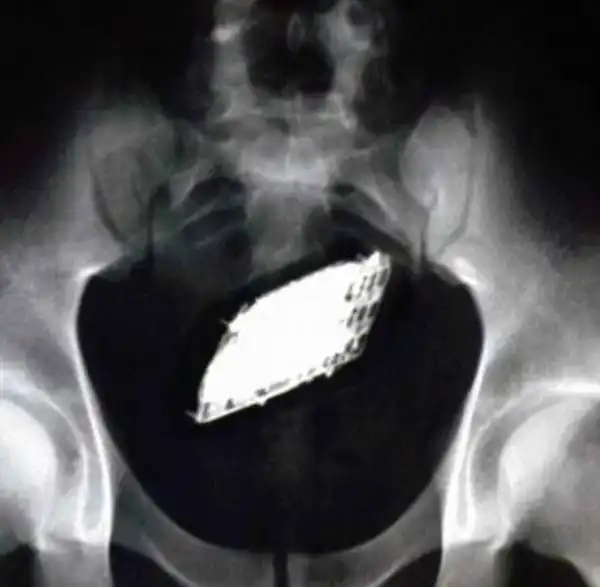

Довольно интересный фотоотчет о том, как и где прячут свои мобильные телефоны

находчивые и весьма креативные заключенные бразильской тюрьмы.